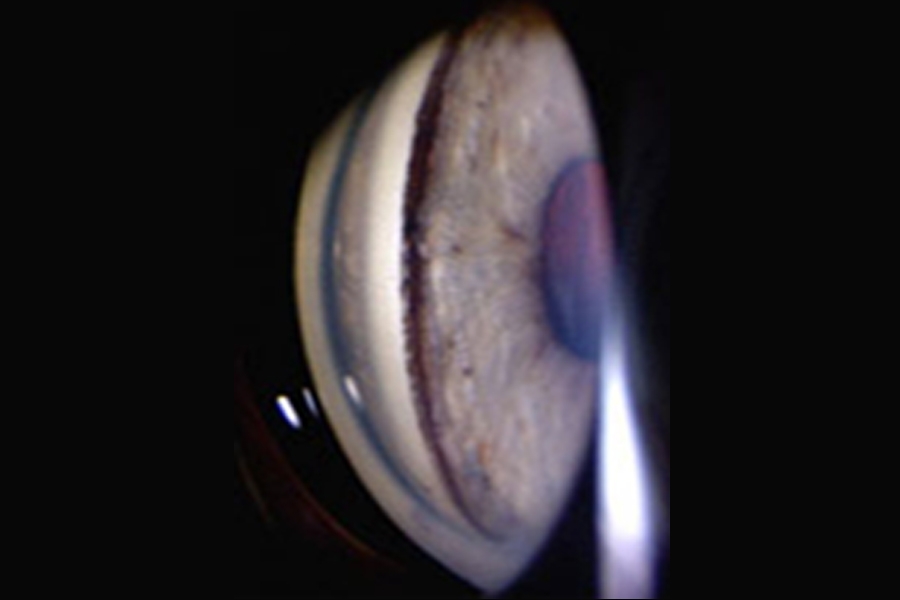

5.2.2.4. Glaucoma Pigmentario

Esta forma poco usual de glaucoma es provocada por la obstrucción del ángulo de drenaje del ojo a causa de la liberación de los gránulos de pigmento del epitelio pigmentario del iris, reduciendo la cantidad de fluido que consigue salir del ojo.

Al tiempo, se da una respuesta inflamatoria contra el bloqueo del ángulo, lo que perjudica el sistema de drenaje.